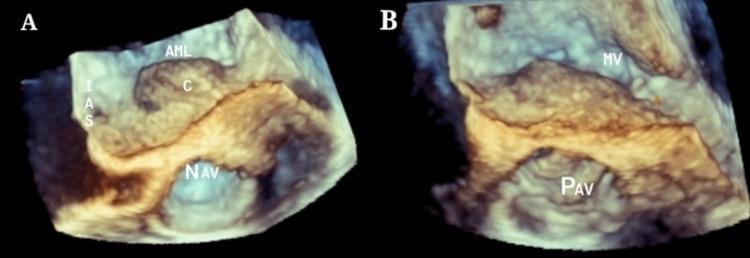

In infective endocarditis, the perivalvular abscess is a known complication with an incidence of more than 22%-29%, but the primary presentation of a healed aortic abscess without any clinical features of infective endocarditis is very rare. These sorts of cases are scarcely documented throughout literature. We present a successful surgical closure of healed perivalvular abscess cavity with aortic valve replacement and mitral valve repair.

在感染性心内膜炎中,瓣周脓肿是一种已知的并发症,发生率超过22% - 29%,但已愈合的主动脉脓肿在没有任何感染性心内膜炎临床特征的情况下首次出现是非常罕见的。这类病例在整个文献中鲜有记载。我们成功地通过主动脉瓣置换和二尖瓣修复对已愈合的瓣周脓肿腔进行了手术闭合。